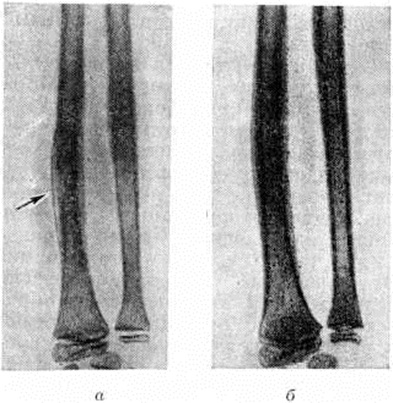

Большую ценность для диагностики представляет рентгенологическое исследование. Наиболее ранним косвенным рентгенологическое признаком острого Остеомиелит является утолщение и деформация мягких тканей, окружающих кость, что можно обнаружить на 2—3-й день заболевания. Начальные проявления периостального костеобразования у маленьких детей можно увидеть в конце первой недели в виде малоконтрастной линейной тени периостальных наслоений рядом с кортикальным слоем метадиафиза поражённой кости. В дальнейшем кортикальный слой начинает разволокняться, вместо него на уровне поражения нарастают новые линейные слоистые периостальные напластования. Лишь на 2—3-й не д. болезни появляются очаги деструкции и острый Остеомиелит может быть уверенно диагностирован.

Такой поздний срок диагностики заставляет искать и апробировать новые методы более раннего распознавания острого Остеомиелит По данным Л.. В. Прокоповой, получить изображение очагов деструкции в кости, а также обнаружить явления периостита и усиление контуров мягких тканей уже на 3—4-й день заболевания удаётся посредством электрорентгенографии (смотри полный свод знаний).

Прогноз в значительной степени зависит от возраста ребёнка, сроков начала лечения и его полноценности. Наиболее благоприятных результатов удаётся достичь у детей в возрасте старше 1 года, когда лечение начато не позднее 3—5-го дня от момента заболевания. В этих случаях воспалительный процесс останавливается, начинается репаративная перестройка кости, приводящая к восстановлению её формы и структуры (рисунок 7). Если лечение начато несвоевременно, то в конце 3-й — начале 4-й недель начинают выявляться признаки перехода острого Остеомиелит в хронический стадию.